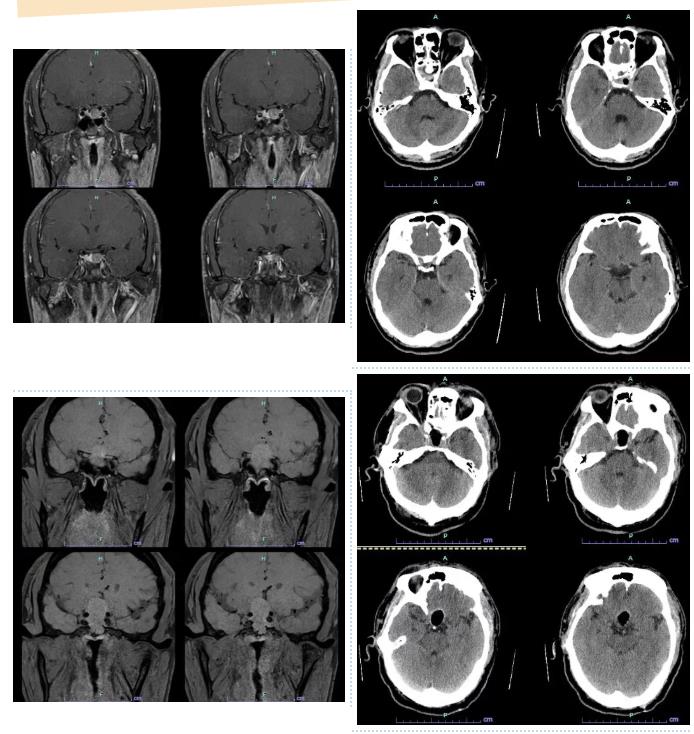

经系统检查,医生发现这并非普通代谢疾病,而是脑中一颗直径约4厘米的垂体瘤在作祟。更关键的是,这是一种生长激素型垂体瘤,肿瘤持续过量分泌生长激素,导致了患者均出现手足增大、面容改变以及继发性糖尿病和高血压,压迫视交叉,视力减退。

手术由神经外科团队主刀,在麻醉科、手术室的密切配合下,经过约3小时的精细操作,肿瘤被完整切除。术中出血量极少,体表没有任何切口。